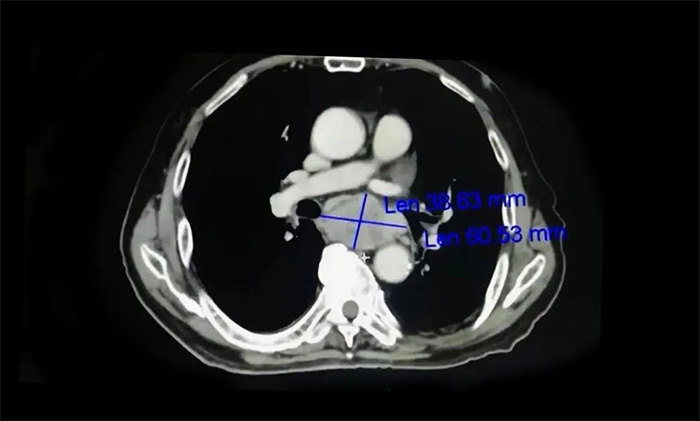

需要提醒的是,食道癌早期患者在就医时常主诉“嗓子处有东西”,这和临床上常见的咽炎症状相似,两者需进行鉴别,要根据患者病史、症状、体征、食管镜检查、影像学检查结果等进行综合判断。其中,食管镜检查加活检病理检查对诊断是否患有食管癌具有重要意义,影像学检查则可为评估肿瘤分期提供可靠的依据。

▲ 影像学检查为评估食管癌分期提供依据